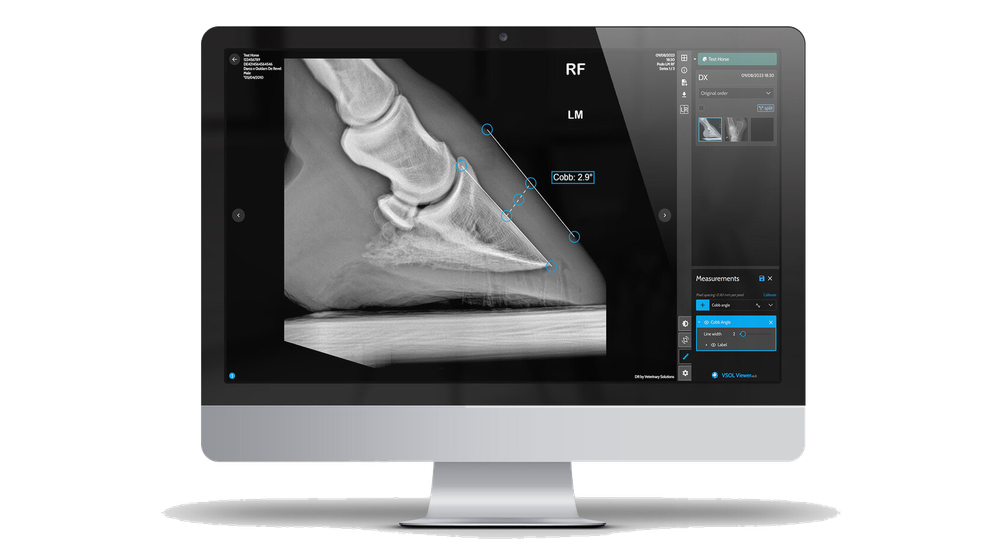

Geavanceerde metingen

Verbeteringen in verwerkingsalgoritmen, zelfs met behulp van kunstmatige intelligentie, helpen bij het stellen van een betere diagnose.